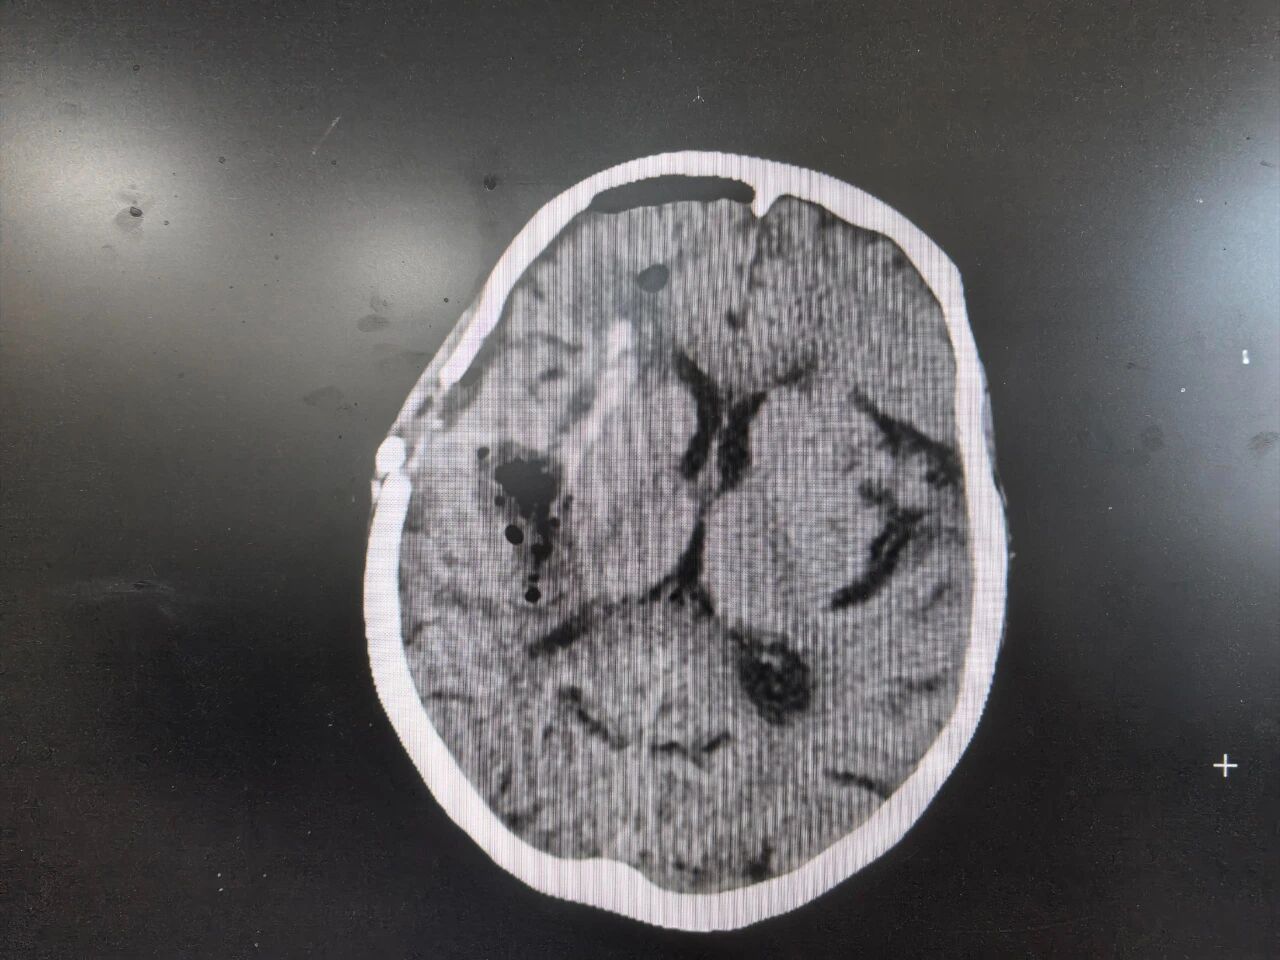

因手术难度大且风险极高,医护团队立即联系玉溪市人民医院神经外科主任顾伟红进行手术支援,最终决定采用“微创颅内血肿清除术”。该项技术只需微小骨窗开窗即可完成,但对手术医生要求近乎苛刻,成败只在毫厘之间,血肿定位必须精准。经过医护团队的紧密协作,手术顺利结束。术后复查颅脑CT颅内血肿清除干净,未见明显新发出血。术后14天,患者各项功能相对稳定,转入普通病房继续治疗。

术后CT:颅骨开窗小,血肿清除干净